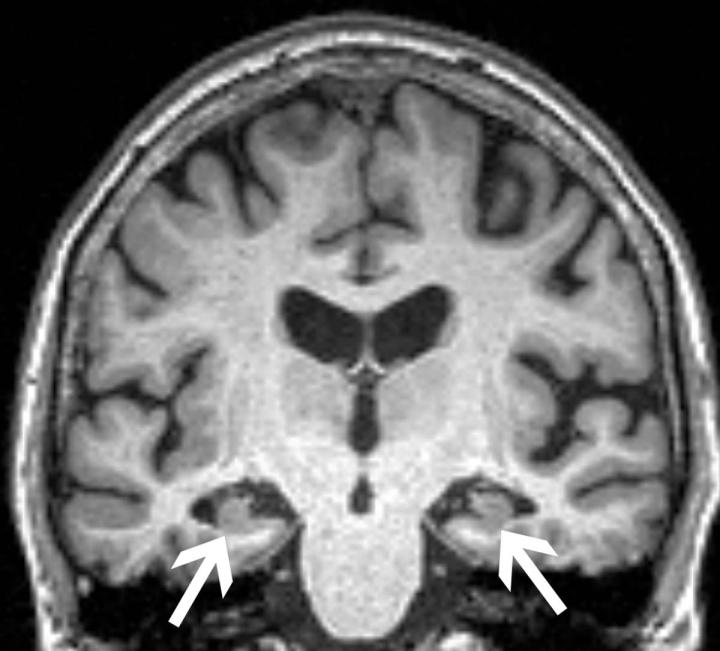

image: Brain MRI of a 72-year-old woman shows loss of volume of the hippocampus (arrows). The patient had all three characteristics, volume loss of the hippocampi, APOE4, and anxiety, found in the study to be associated with progression from mild cognitive impairment to dementia.

"We know that volume loss in certain areas of the brain is a factor that predicts progression to Alzheimer's disease," said study senior author Maria Vittoria Spampinato, M.D., professor of radiology at the Medical University of South Carolina (MUSC) in Charleston. "In this study, we wanted to see if anxiety had an effect on brain structure, or if the effect of anxiety was independent from brain structure in favoring the progression of disease."

The researchers obtained brain MRIs to determine the baseline volumes of the hippocampus and the entorhinal cortex, two areas important to forming memories. They also tested for the presence of the ApoE4 allele, the most prevalent genetic risk factor for Alzheimer's disease. Anxiety was measured with established clinical surveys.

As expected, patients who progressed to Alzheimer's disease had significantly lower volumes in the hippocampus and the entorhinal cortex and greater frequency of the ApoE4 allele. Most notably though, the researchers found that anxiety was independently associated with cognitive decline.